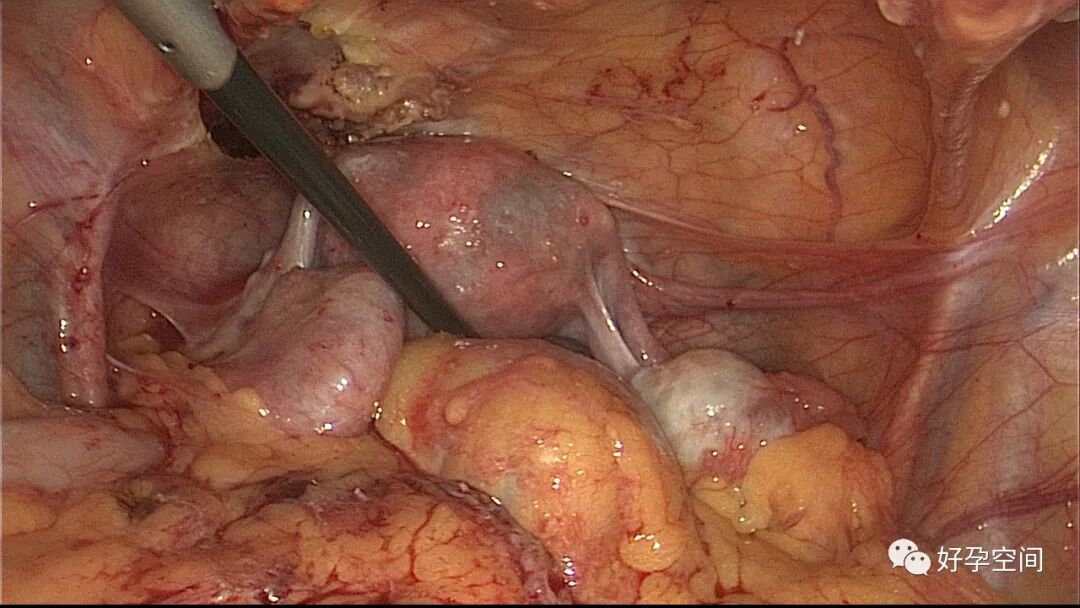

病例1:患者24岁,原发不孕,造影示双侧输卵管堵塞,否认结核病史,无结核病家族史。2022年4月以不孕症收入院手术,术前化验检查无明显异常,胸片示左肺下叶内带稍高密度结节影。行宫腹腔镜探查,宫腔被覆一层棉絮状质脆增生组织,宫腔狭小,宫壁僵硬。腹膜及大网膜广泛分布粟粒样结节,左侧输卵管充满干酪样组织及灰色脓液。

子宫内膜结核是由结核分枝杆菌在子宫内膜部位种植引起的炎症,是仅次于输卵管结核的常见女性生殖器结核。子宫内膜结核常由输卵管结核蔓延而来,多继发于盆腔腹膜结核或肺结核。子宫内膜结核的超声表现主要为:子宫内膜回声不均匀、宫腔内结节样病灶、宫腔内强回声灶、单纯的子宫内膜薄等。盆腹腔超声显示输卵管炎性表现:输卵管增粗、肥厚、扭曲、僵硬、输卵管积液积脓、卵巢旁混合性包块、输卵管系膜囊肿、盆腔包裹性积液等。术中所见:盆腹腔组织粘连、盆腹腔粟粒样结节、结核球、脓肿等,输卵管伞端烟斗样外翻,输卵管内充满淡黄色干酪样或豆渣样组织。宫腔镜显示宫腔狭窄、宫壁僵硬、宫内膜肉芽肿样增生、内膜质脆易刮除、干酪样组织、脓液等。